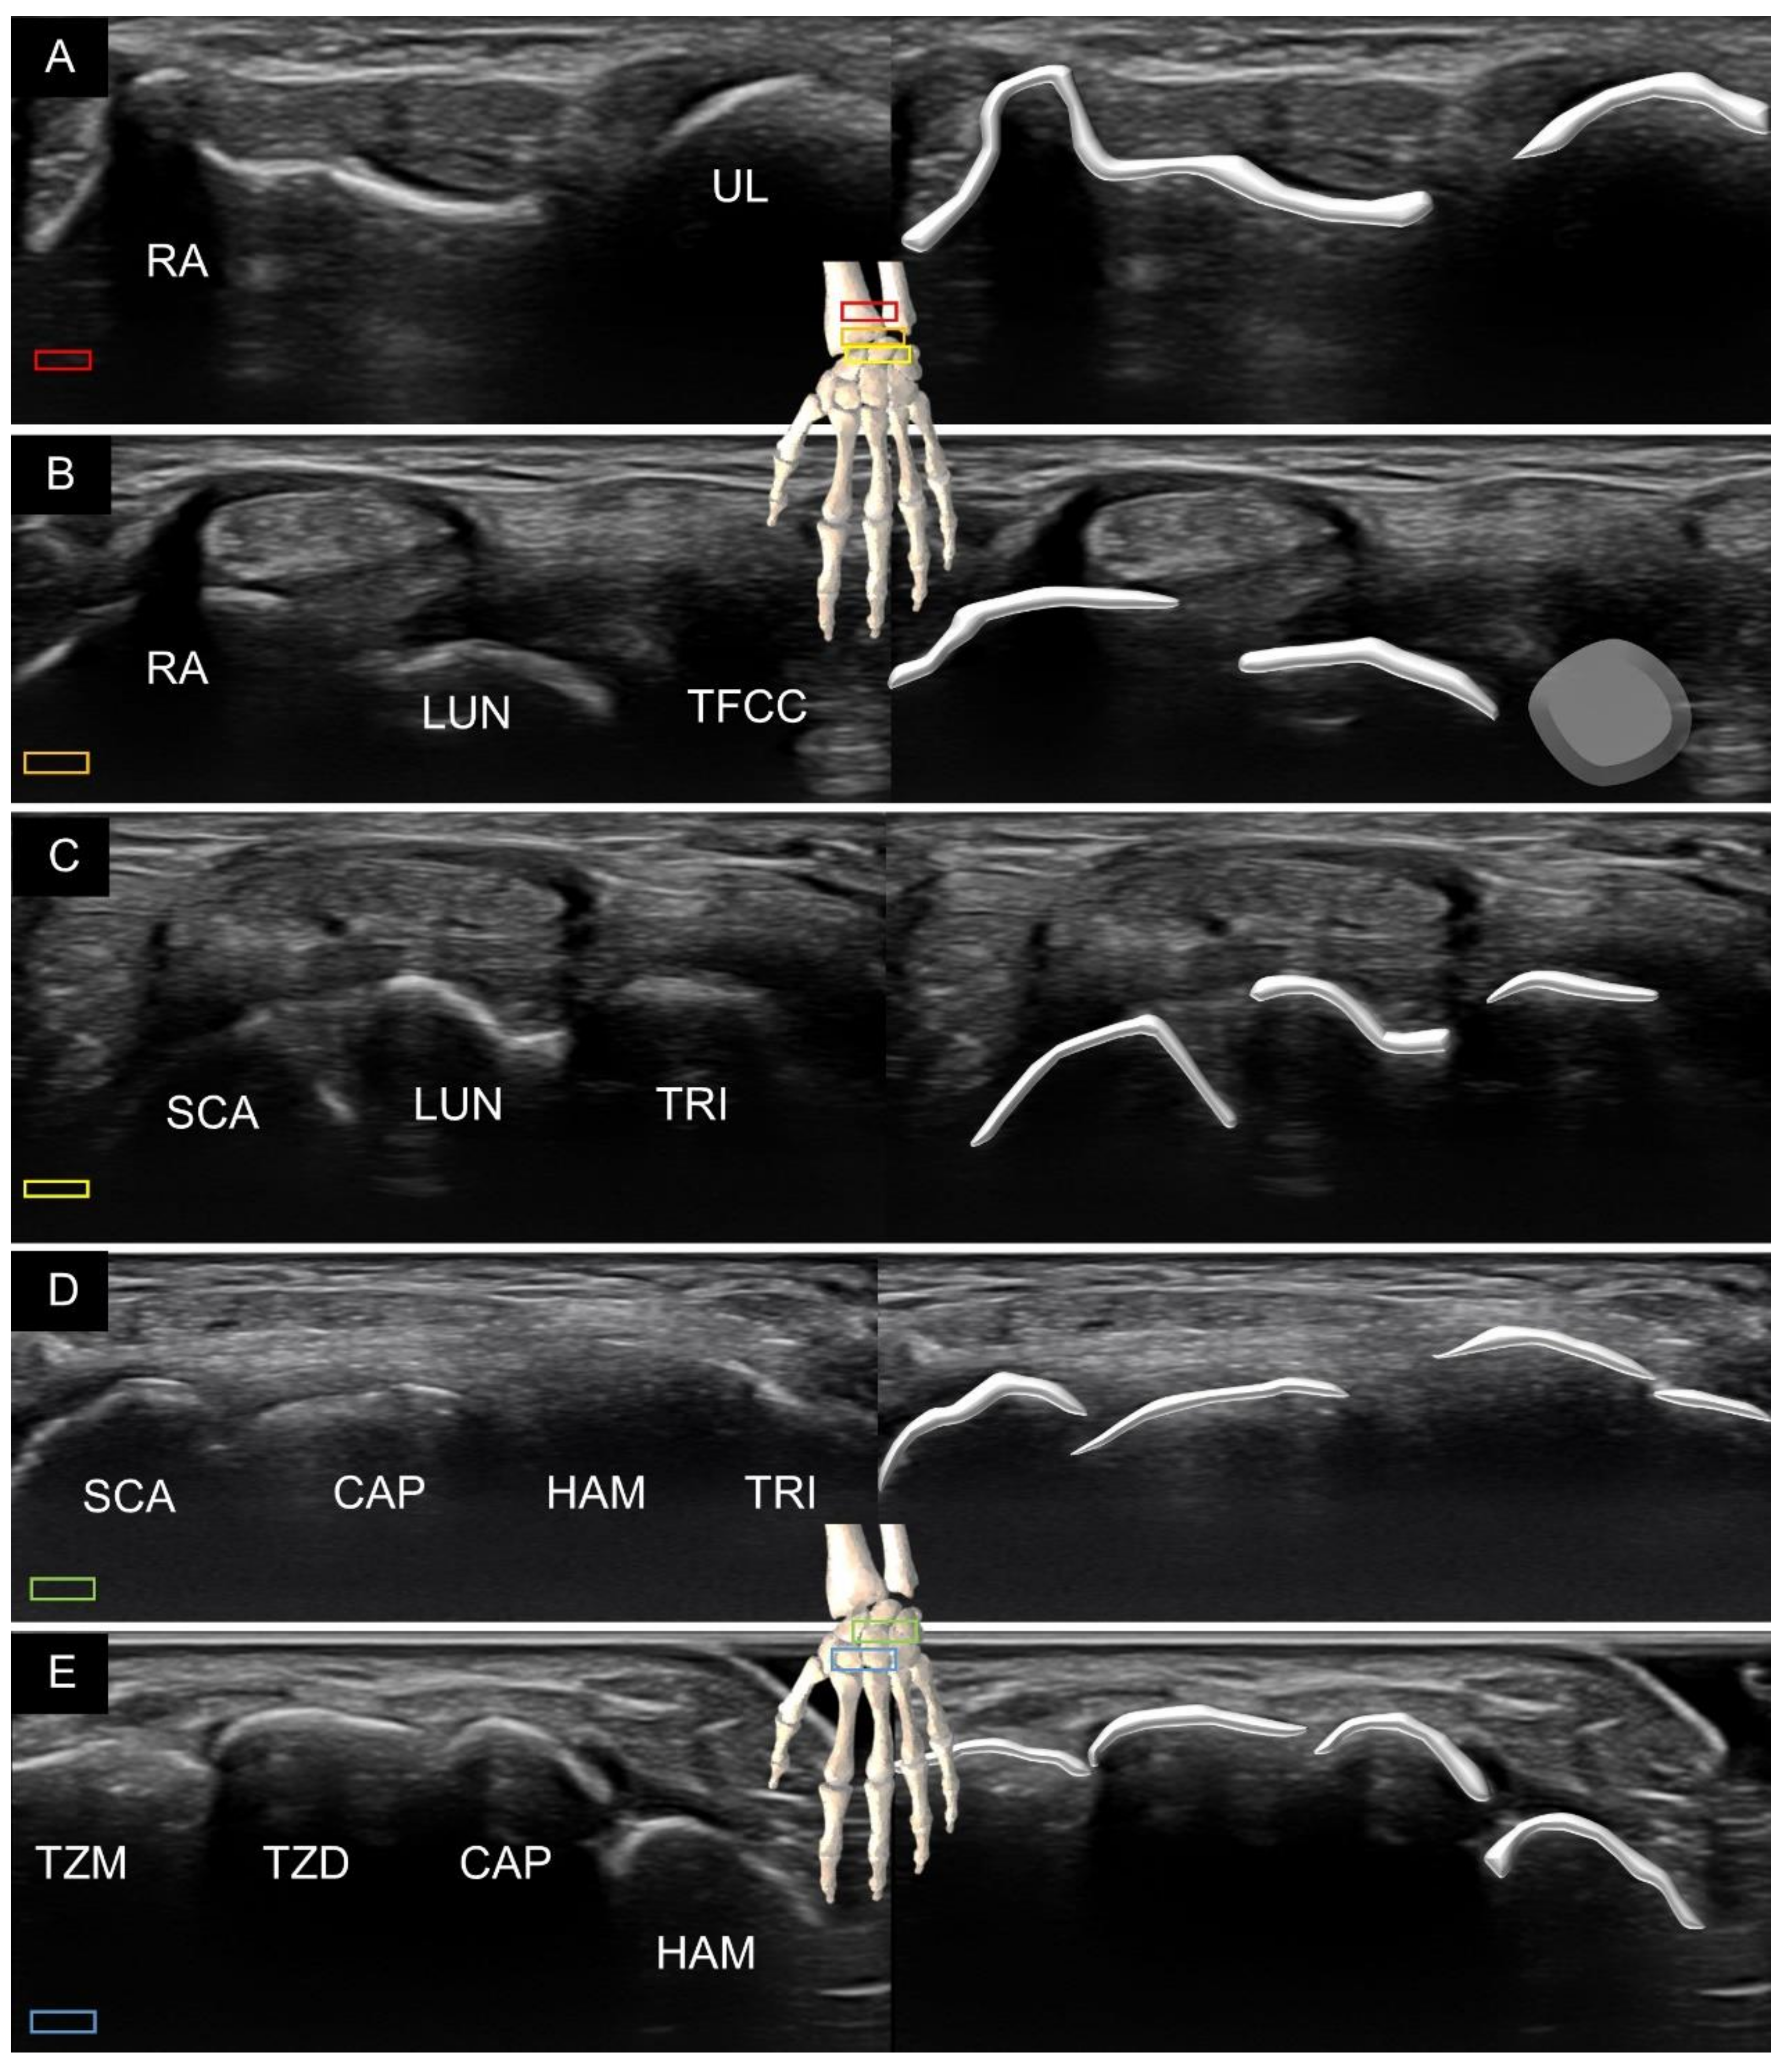

3.1. Attachment to the Capitate

3.2. Attachment to the Lunate

3.3. Attachment to the Triquetrum

4. Sonoanatomy of Volar Intrinsic Carpal Ligaments